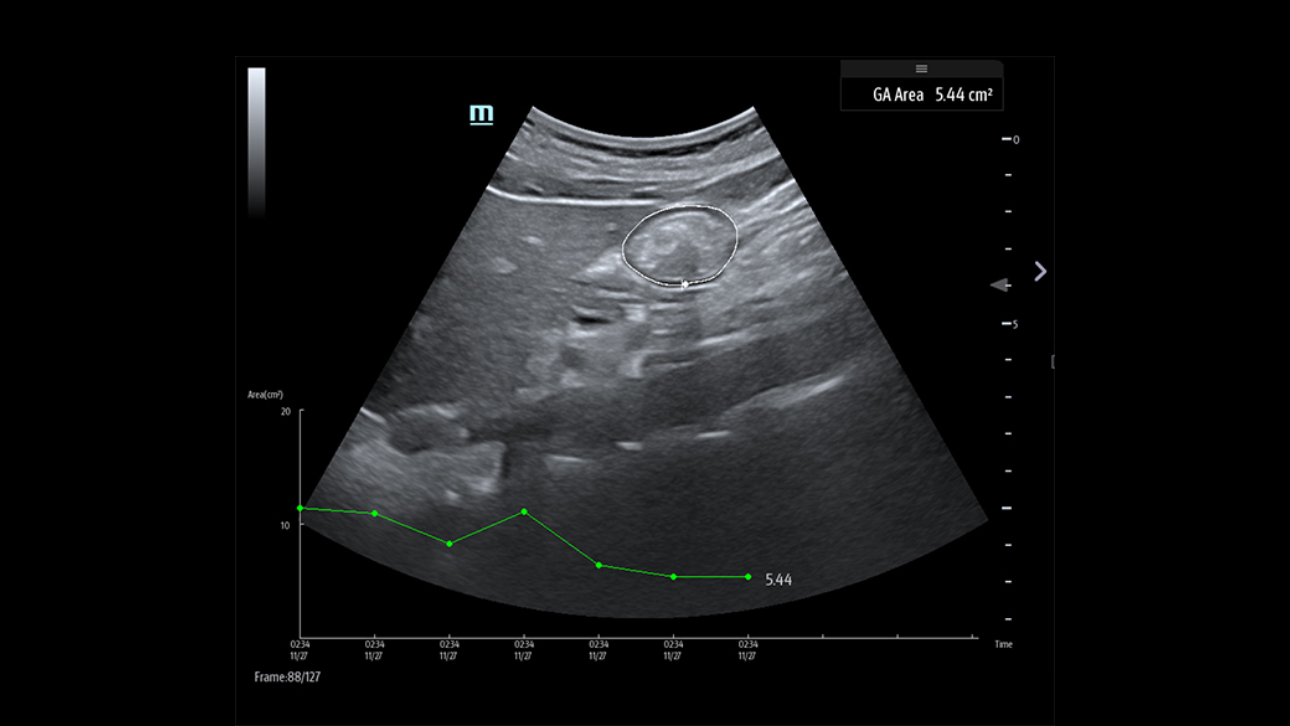

The TE9 Ultrasound System is designed to expand imaging capabilities across point-of-care environments including anaesthesia, emergency, and critical care.

A large clear touchscreen, superior imaging and intelligent diagnostic tools allow the TE9 to support clinical efficiency and diagnostic confidence in high acuity settings. Its compatibility with a wide range of transducers means it can easily adapt to meet point-of-care needs and support a wide range of procedures and diagnostics.

When part of a connected workflow, the TE9 represents a future-proof point-of-care ultrasound solution that can be deployed quickly and reliably ŌĆō supporting clear and reproduceable results.